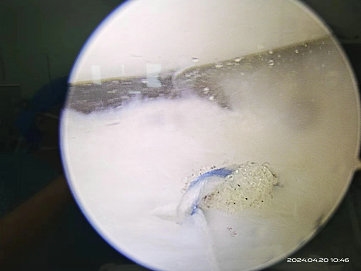

由于患者年轻,活动量大,且新鲜损伤,主任医师闫鹏为陈某实施了膝关节镜下半月板缝合修复术,手术仅需要做2个5mm小切口,术中直视下证实了患者半月板撕裂。手术非常顺利,最大程度保留了患者的半月板,且切口很小,不影响美观。

▲ 术中镜下所见